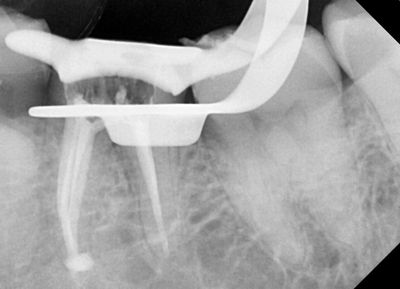

Root canal therapy, also known as endodontic treatment, becomes necessary when the dental pulp inside the tooth becomes infected or inflamed due to deep decay, cracks, or trauma. This procedure involves removing the infected pulp, cleaning the inside of the tooth, and sealing it to prevent further infection.